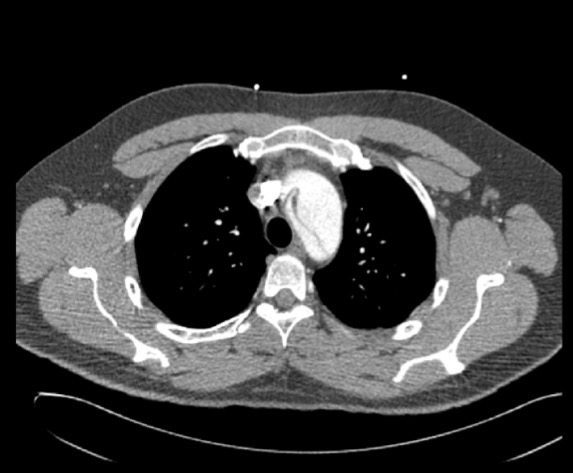

3. En nuestro caso tanto el electrocardiograma que no presenta datos de isquemia miocárdica aguda (descenso del segmento ST menor a 1 mm con onda T negativa asimétrica en I-II-aVL, V5-V6 sugestivo de sobrecarga sistólica de ventrículo izquierdo) como los hallazgos de ensanchamiento del mediastino superior en la radiografía de tórax aumentan la probilidad de que se trate de un síndrome aórtico agudo (SAA). Dada la elevada morbimortalidad que presenta esta entidad es indispensable confirmar o excluir su diagnóstico, siendo para ello fundamental las técnicas de imagen, como son la ecocardiografía (particularmente el ecocardiograma transesofágico) y la tomografía computerizada (TC). En casos de baja probabilidad clínica podría considerarse la determinación del dímero D debido a su elevado valor predictivo negativo para descartar esta entidad. La ecocardiografía es de gran utilidad en pacientes inestables o en casos de alergia al contraste iodado (utilizado en el TC). Por otro lado, el angio-TC (con una sensibilidad y especificidad > del 93 y 83%, respectivamente) es la técnica de imagen más utilizada para el diagnóstico del SAA, en especial en la disección de aorta. Dado que nuestro paciente inicialmente no presentaba deterioro hemodinámico solicitamos un angio-TC (ver imagen) que mostró un aneurisma de aorta ascendente con flap intimal que se origina en aorta ascendente a la salida del tronco braquiocefálico derecho hasta la aorta descendente inmediatamente distal a la salida de la arteria subclavia izquierda, compatible con Disección tipo A de Stanford. Es importante recordar que los SAA puede presentarse de formas muy diversas (infarto agudo de miocardio, insuficiencia aórtica aguda, taponamiento cardíaco, síncope, ictus isquémico o AIT, alteraciones perfusión periférica y crisis hipertensiva).